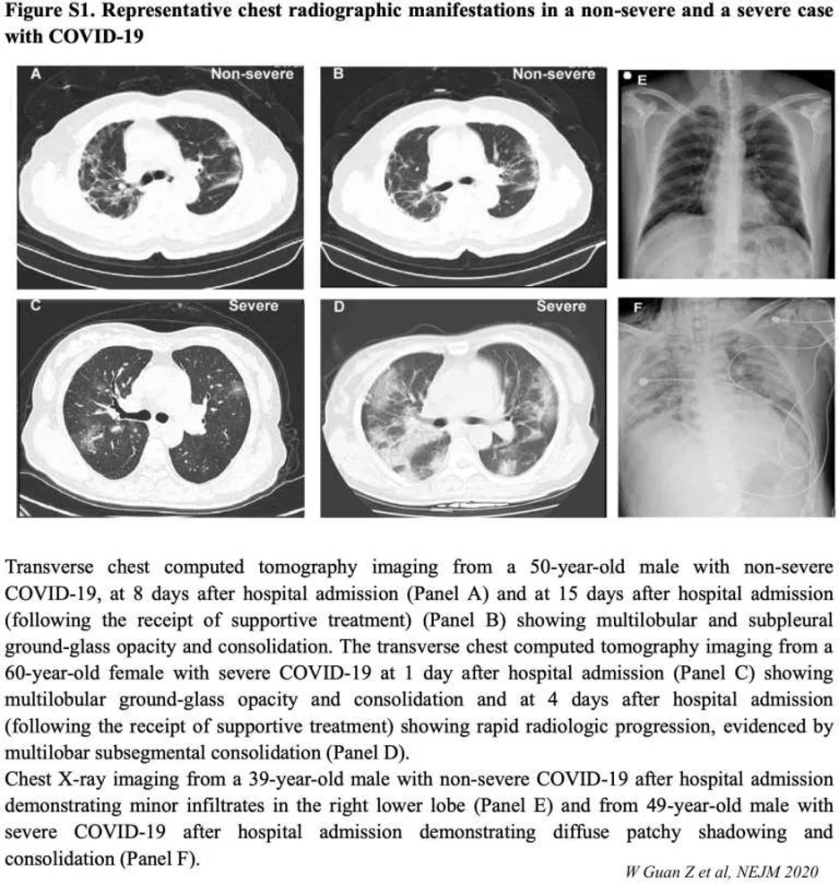

image-9